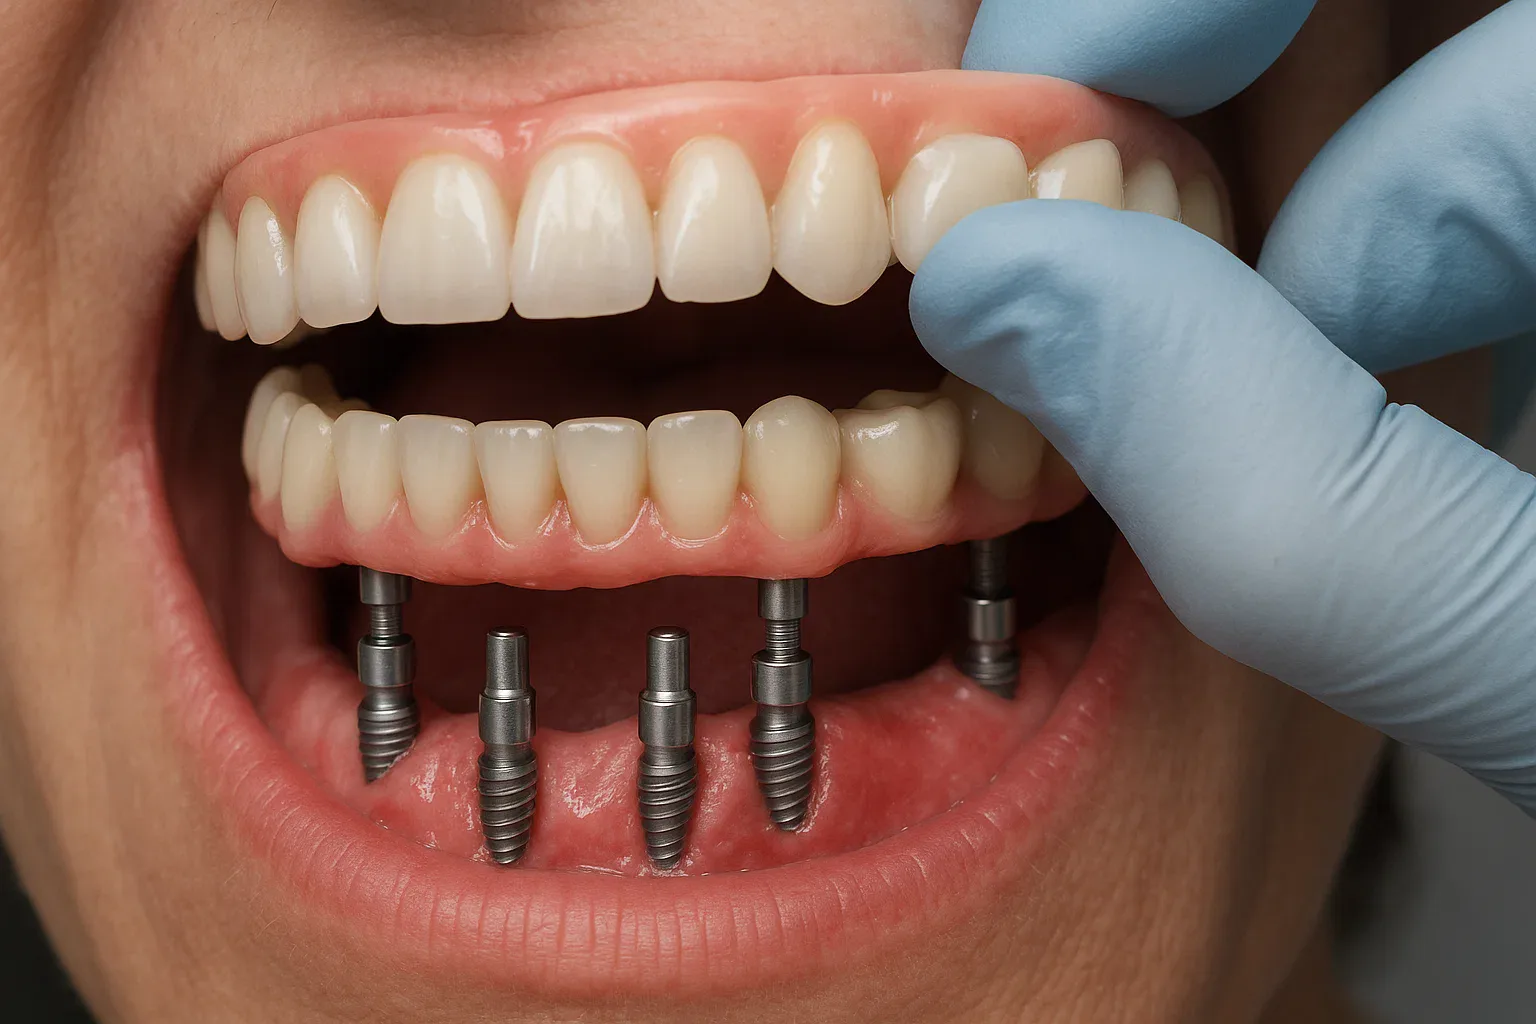

All on 4, tamamen dişsiz veya dişlerini kaybetmek üzere olan hastalar için geliştirilmiş ileri bir implant sistemidir. Bu yöntemde, bir çenedeki tüm dişleri yeniden inşa etmek için sadece 4 adet implant kullanılır.

yerleştirilir. Bu özel açılandırma, kemik hacmi az olsa bile yüksek stabilite sağlar.

Tedavi günü geçici sabit protez takılabilir ve hasta aynı gün yeni dişleriyle eve dönebilir.

Bu nedenle All on 4, literatürde “Aynı Gün Sabit Diş” tedavisi olarak da bilinir.

Hasta aynı gün sabit geçici protezlerine kavuşur.